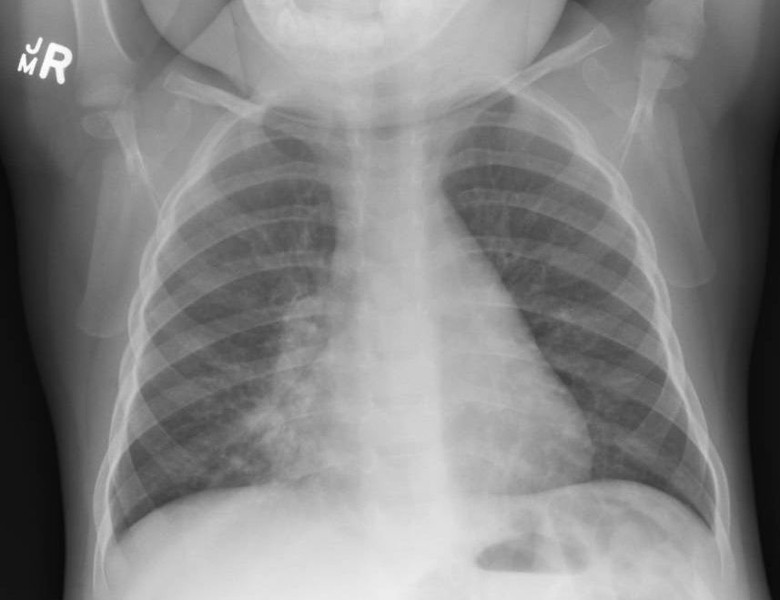

21 month old with SpO2 of 89% on room air and a temperature of 37.4°C increased WOB and auscultory findings........what lobe is the issue in?

R middle lobe consolidation / collapse

The chest X-ray shows obliteration of the right heart border in keeping with right middle lobe consolidation or collapse obscuring the r heart border